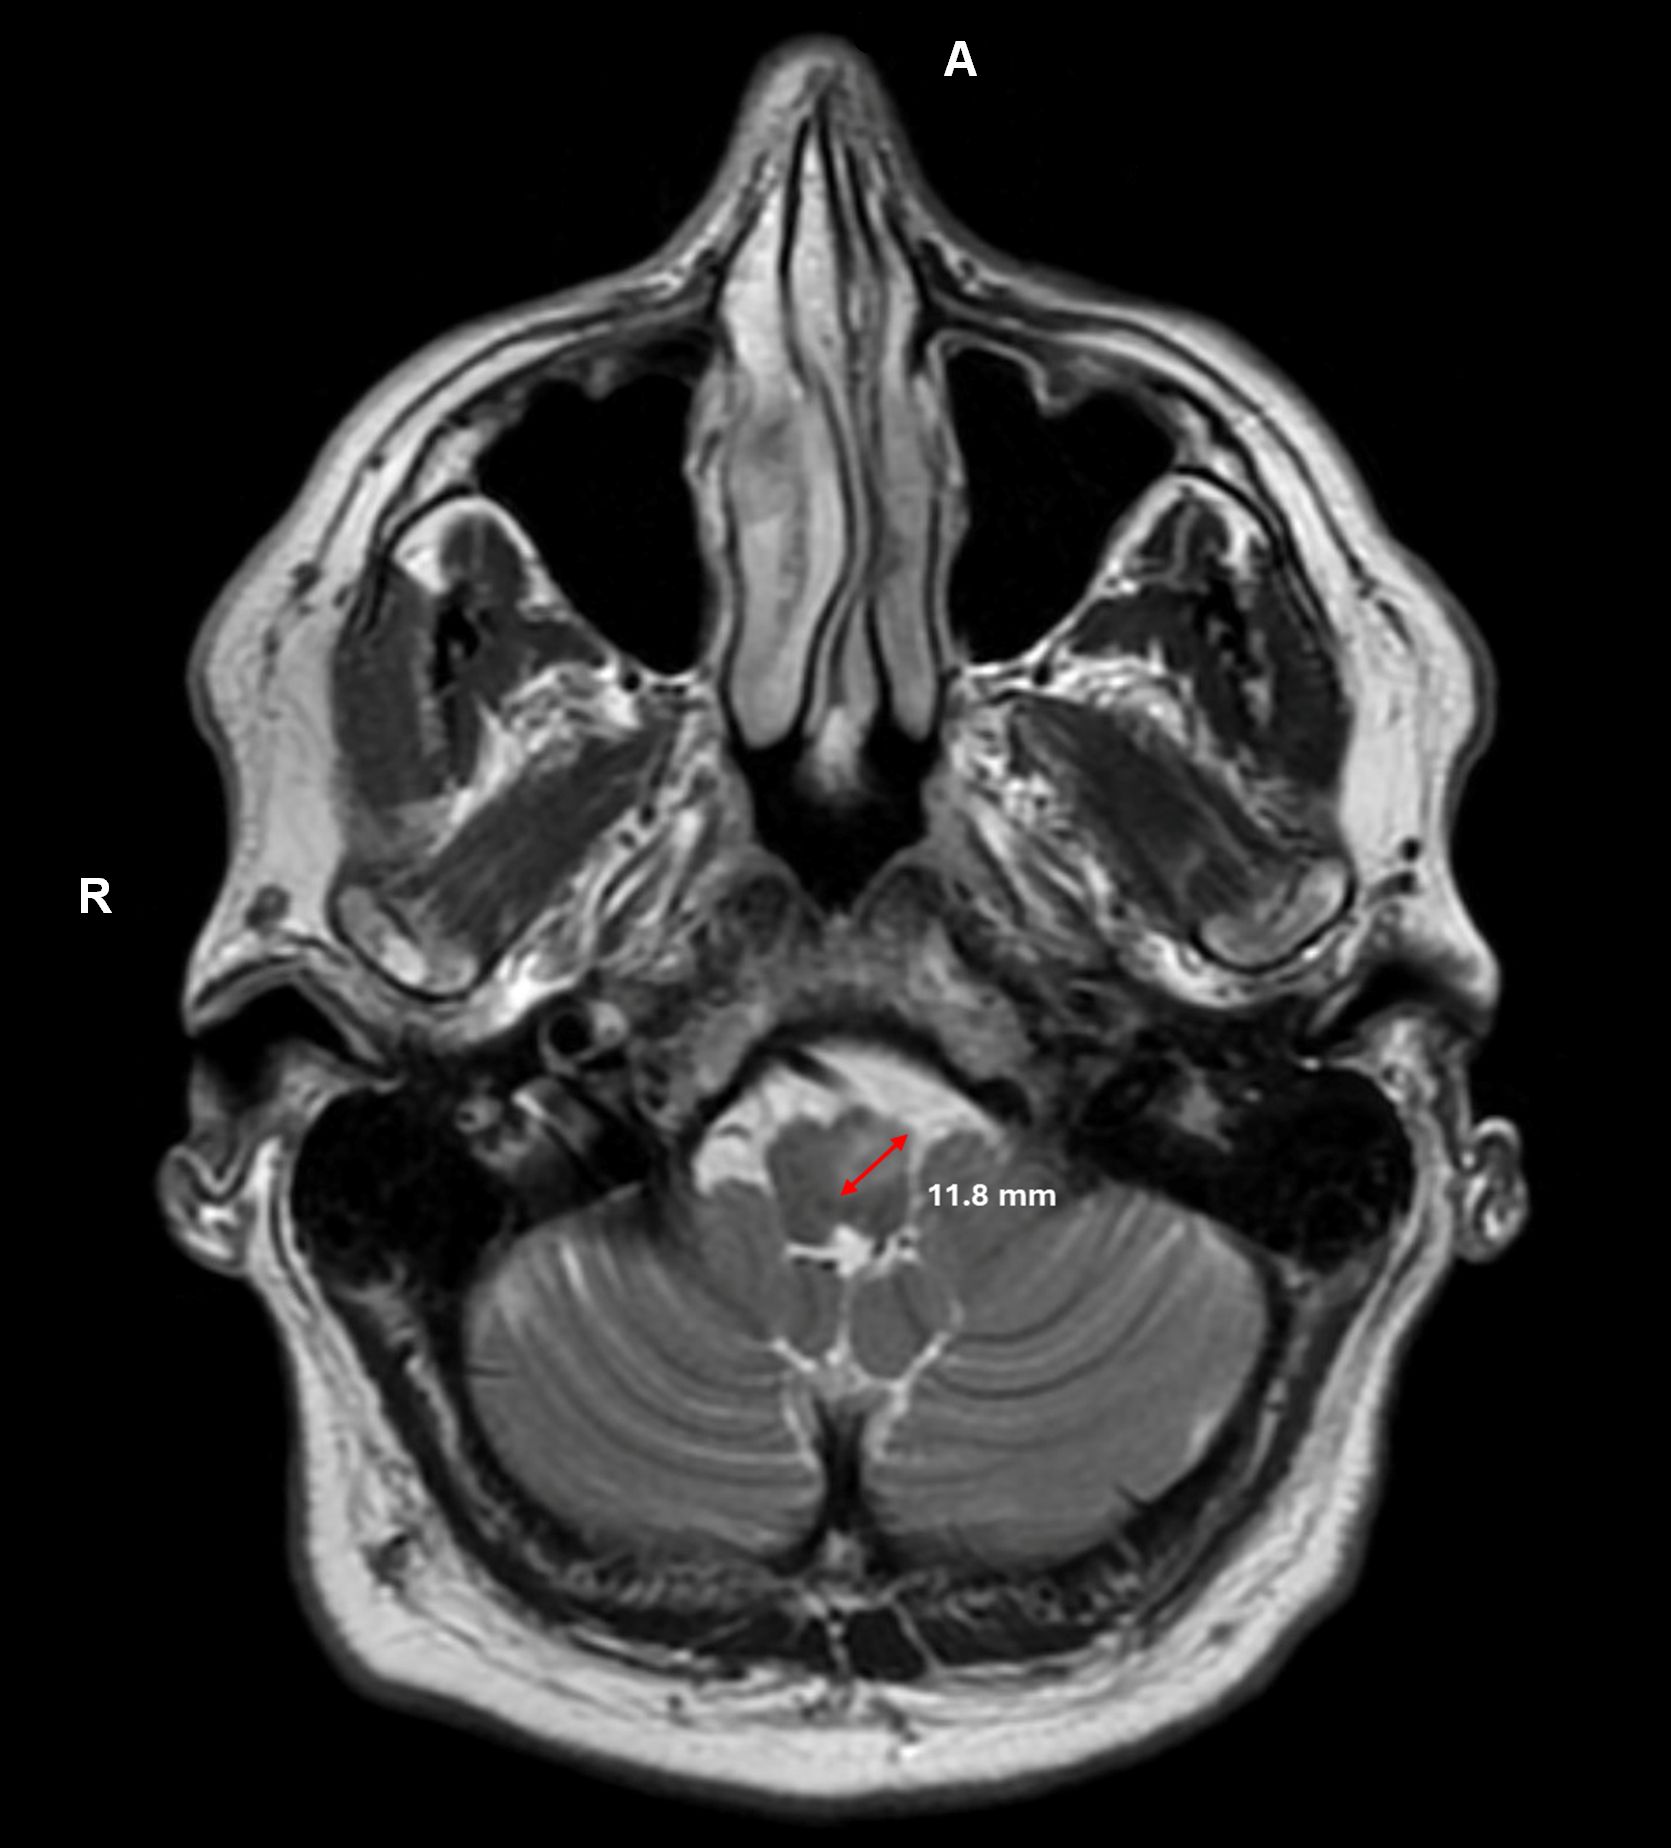

Results: A 64-year-old right-handed male with a history of brainstem hemorrhage presented with binocular horizontal diplopia, oscillopsia and dysphonia one year post-hemorrhage. Neuro-ophthalmologic examination revealed varying torsional nystagmus with horizontal components. Torsion was clockwise in left gaze, counterclockwise in right gaze, and alternating between clockwise and counterclockwise in primary gaze. Palatal myoclonus synchronized with nystagmus was observed. Brain MRI demonstrated T2 hyperintensity in the left paramedian anterior medullary region [Figure 1], likely reflecting hypertrophic olivary degeneration in conjunction with gliosis and susceptibility artifact from prior hemorrhage at the level of the superior left cerebellar peduncle disrupting the Guillain-Mollaret triangle. A four-month trial of memantine provided no benefit. The patient was referred to vision rehabilitation, achieving modest improvement.

T2 hyperintensity of ION